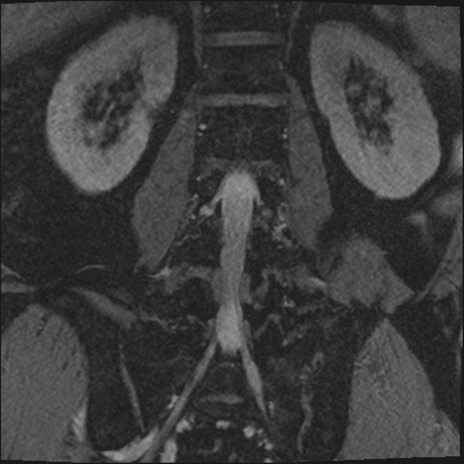

【整形】TIPS症例2 腰椎MRI 3D(冠状断像)

【症例】70歳代男性

【主訴】左下肢痛

【現病歴】2週間前くらいから腰痛、左下肢痛あり。左臀部から大腿、下腿外側のしびれが常時ある。歩行とともに同部位の痛みあり。

【身体所見】Lasegue70-/60+、Bragard-/±、PTR ±/±、ATR -/-、IP 5/5、TA 5/4、TS 5/5、EHL 右第1足趾なし/3、FHL 5/5、hypersthesia(-)、足背動脈触知良好

異常所見と診断は?